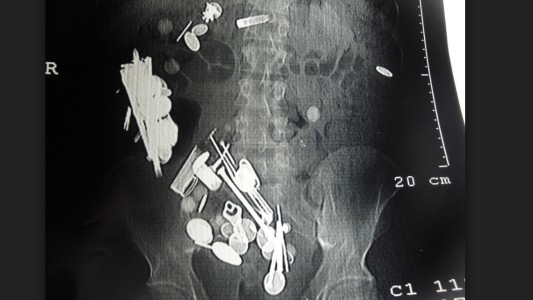

El extraño caso del hombre con depresión que se comió 263 monedas, 150 clavos y una correa para perros